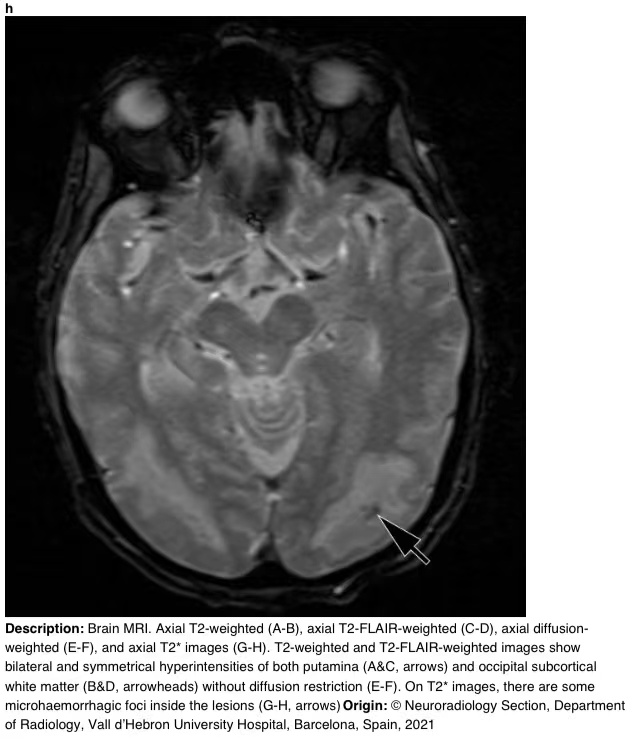

在16天的随访中,脑部MRI显示壳核和枕下皮质下白质上对称的T2/FLAIR高信号。T2图像显示病变内有微出血(图3)。

图3h

图3 a-h 脑部核磁共振成像。轴向T2加权(A-B)、轴向T2 FLAIR加权(C-D)、轴向弥散加权(E-F)和轴向T2图像(G-H)。T2加权和T2 FLAIR加权图像显示双侧和对称的壳核高信号(A和C,箭头)和枕下皮质下白质高信号(B和D,箭头),无弥散限制(E-F)。在T2图像上,病变内有一些微出血病灶(G-H,箭头)。